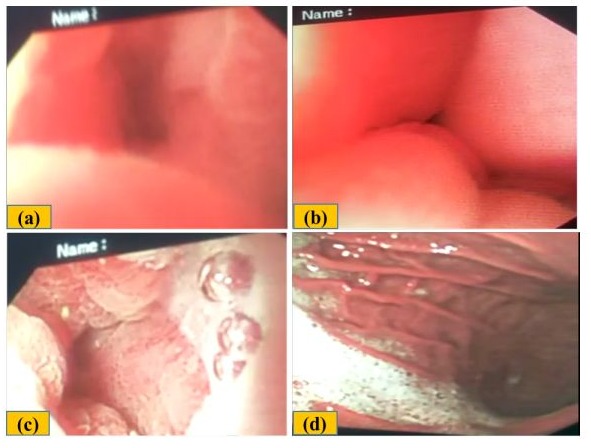

Figure 1. (a) Inflammation and erosions at gastroesophageal junction and a small Barrett’s (Arrow). (b) Incomplete Schatzki’s ring (Arrow). (c) Moderate diffuse erythema with mild erosions in the antrum. (d) Pylorus and initial part of duodenum appear normal.

Figure 2: (a & b) Normal gastroesophageal junction, no erosions, Barrett, or Schatzki’s ring (c) Erosions in antrum, possibly age related (d) Normal pylorus.